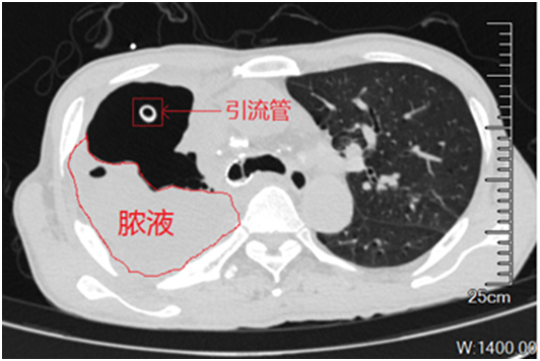

脓胸最常见的致病菌是铜绿假单胞菌。在可以用来治疗该细菌的药物中,碳青霉烯类抗生素是抗菌谱最广、抗菌活性最强的药物。不幸的是,该患者脓胸分泌物培养出来的铜绿假单胞菌,不仅对常用的抗生素耐药,而且对碳青霉烯类也耐药。在近2个月的各种抗生素治疗后,患者的脓胸没有得到控制:支气管胸膜瘘还一直往外漏气漏液,右边胸腔一半都是脓液,引流脓液的管子还在咕噜咕噜的冒着气体。卢洪洲教授团队经过会诊,仔细评估,决定给患者进行噬菌体治疗。噬菌体是一种以细菌作为宿主的病毒,显微镜下它有一个菱形的脑袋、长长的脖子,还有六个爪子,像个机器人一样。它会先吸附在细菌表面,然后把自己的DNA注入细菌体内,DNA在细菌体内大量复制使细菌裂解,从而杀灭细菌。随着细菌耐药问题日趋严峻,噬菌体疗法成为耐药细菌治疗的一种潜在的补充或替代疗法。

经过24天的雾化吸入和胸腔注射噬菌体治疗,患者的胸水未再培养出耐碳青霉烯铜绿假单胞菌,说明他的感染已经得到控制。此后,患者病情好转,康复出院。